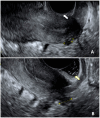

Endometriosis has a prevalence of 10% worldwide in premenopausal women. Probably, endometriosis begins early in the life of young girls, and it is commonly diagnosed later in life. The prevalence of deep infiltrating endometriosis (DIE) in adolescence is currently unknown due to diagnostic limits and underestimation of clinical symptoms. Dysmenorrhea is a common symptom in adolescents affected by DIE, often accompanied by dyspareunia and chronic acyclic pelvic pain. Ultrasonography-either performed transabdominal, transvaginal or transrectal-should be considered the first-line imaging technique despite the potential for missed diagnosis due to early-stage disease. Magnetic resonance imaging should be preferred in the case of virgo patients or when ultrasonographic exam is not accepted. Diagnostic laparoscopy is deemed acceptable in the case of suspected DIE not responding to conventional hormonal therapy. An early medical and/or surgical treatment may reduce disease progression with an immediate improvement in quality of life and fertility, but at the same time, painful symptoms may persist or even recur due to the surgery itself. The aim of this narrative review is to report the prevalence of DIE in adolescents, describe the pathogenetic theories and discuss the management in adolescent women, including the challenging road to diagnosis and the treatment alternatives.